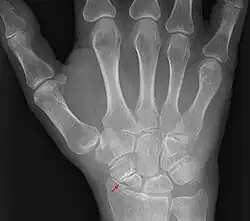

Eine Kahnbeinpseudarthrose ist eine Pseudarthrose vom Os scaphoideum des Handgelenks.

Das Kahnbein ist der biomechanisch wichtigste Knochen der Handwurzelknochen. Eine Kahnbeinpseudarthrose kann beim Ausbleiben der Bruchheilung einer Fraktur des Kahnbeines entstehen. Bei der konservativen, nicht operativen Behandlung werden Pseudarthroseraten von 23 % berichtet,[3] bei der operativen Behandlung wird in der Literatur von Pseudoarthroseraten zwischen 5 und 15 % berichtet.[4] Die Kahnbeinpseudarthrose hat somit im Wesentlichen zwei Ursachen:

- Die Kahnbeinfraktur bleibt unerkannt, da sie im Röntgen nicht vom behandelnden Arzt erkannt wird, oder der Patient nicht ins Spital ging.